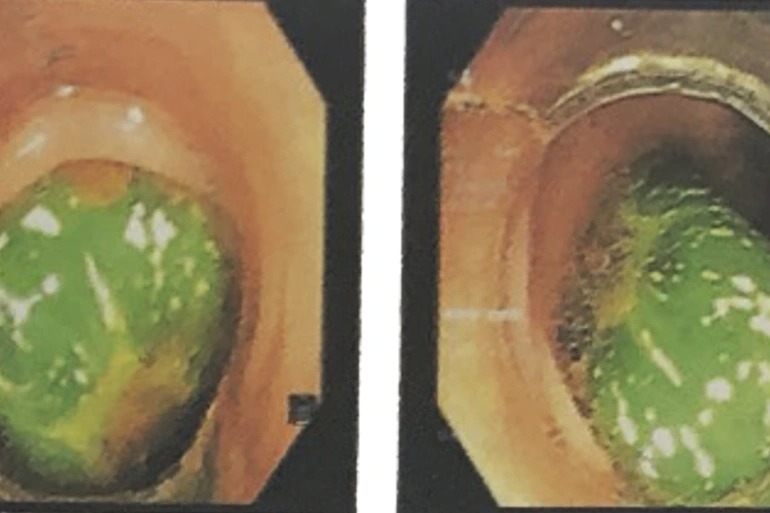

Các bác sĩ khoa Cấp cứu, Bệnh viện Nguyễn Tri Phương tiếp nhận và chỉ định nội soi trực tràng. Qua nội soi trực tràng cấp cứu, các bác sĩ xác định quả dưa leo dài hơn 10 cm nằm sâu trong lòng trực tràng. Nhưng do kích thước dị vật quá lớn, tiến hành gắp qua nội soi thất bại, bác sĩ nội soi đề nghị hội chẩn với bác sĩ khoa Ngoại tiêu hóa.

Theo Dân Trí dẫn lời TS.BS. Lê Huy Lưu, Phụ trách điều hành khoa Ngoại Tiêu hóa, Bệnh viện Nguyễn Tri Phương cho biết, căn cứ vào thăm khám vùng hậu môn và kết quả nội soi cho thấy dị vật là quả dưa leo thuôn dài, rất chắc, bề mặt tương đối trơn láng, chưa ghi nhận chảy máu vùng hậu môn trực tràng. Sau khi được tư vấn và giải thích về tình trạng cần phải phẫu thuật, bệnh nhân nhanh chóng được chuyển đến khoa Phẫu thuật - Gây mê hồi sức.

Quá trình phẫu thuật, các bác sĩ xác định thấy đầu quả dưa leo trượt xuống gần hậu môn nên đã dùng kẹp có móc, kẹp chặt nhẹ nhàng, xoay vòng và cẩn thận kéo ra ngoài. Cuối cùng, dị vật là quả dưa leo dài hơn 10cm được lấy ra ngoài thành công, không có chảy máu từ đường tiêu hóa dưới.